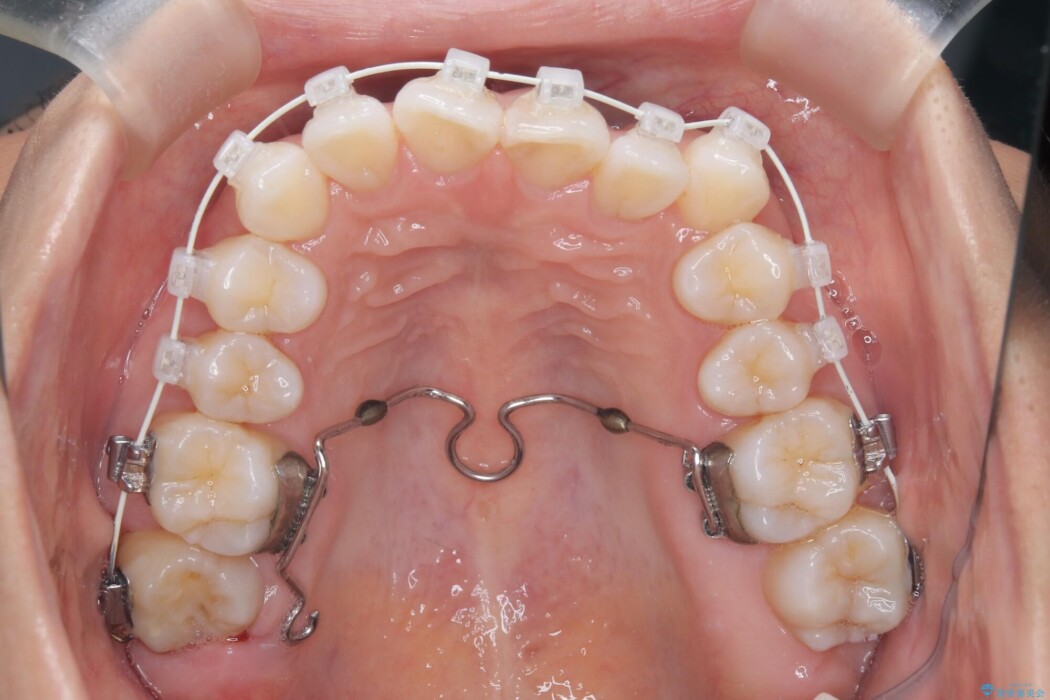

全体的にスペース不足ではありましたが、患者様は抜歯をしたくないとのご要望だったため、上顎の裏側に「トランスパラタルアーチ(TPA)」という装置を装着し、奥歯の幅を調整しながらスペースを確保する計画を立案。

トランスパラタルアーチを用いて右上7番目の歯を内側へ誘導し、正しい位置へと修正しました。

まずはこの装置で奥歯の土台を安定させつつ、ワイヤー装置による繊細な歯の移動を組み合わせることで、非抜歯で歯列全体のアーチを整えていきました。シザーズバイトが解消されたことで、奥歯でしっかりと物を噛めるようになり、顎の動きもスムーズに改善されました。